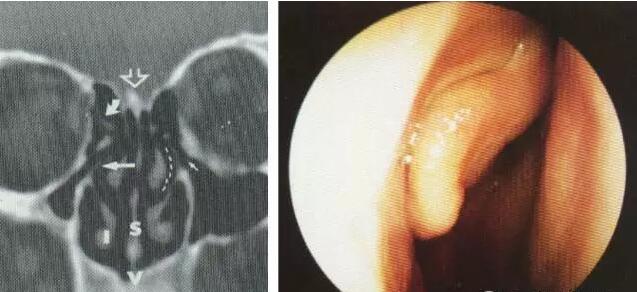

筛顶与筛板的联接方式

左:倾斜式连接 右:高台式连接

筛顶与筛板的连接顶面观(高台式)

筛顶与筛板连接的研究(100具颅骨)

高台式连接与手术

筛凹内侧壁薄而脆,易损伤